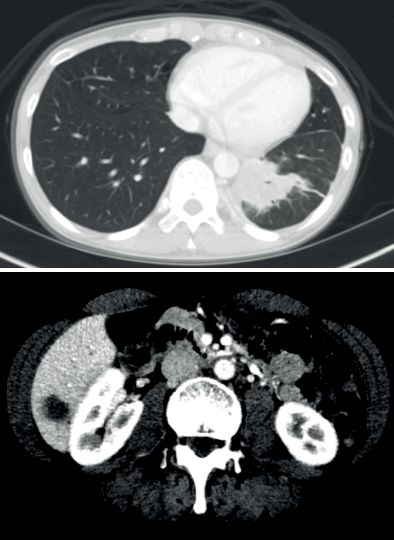

患者三:IRF2BP2-NTRK1融合非小细胞肺癌的持久反应

31岁女性被诊断患有IV期NSCLC腺癌,颈部左侧,腋窝和右乳内淋巴结转移,对腹部和锁骨上窝的放射治疗后,患者出现周围神经病变,颈部疼痛和粘膜炎,对所有先前的全身治疗均无反应,包括顺铂,培美曲塞和多西紫杉醇。

FoundationOne检测具有NTRK融合基因,接受larotrectinib 100 mg BID,在第56天确认完全反应,所有症状完全消除,反应持续时间> 20.27个月,患者仍在接受治疗,未报告严重不良事件。